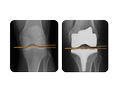

Normal shapes. Normal position. Normal motion

Reproduction of optimal kinematic patterns during TKA could be instrumental in improving patient satisfaction.1 The solution to providing patients with better overall satisfaction and functionality is to design an implant as close to the normal knee as possible.

The JOURNEY II System has been shown to restore anatomical shape, position and motion.2-6 This anatomical restoration can provide superior clinical outcomes that can lead to high patient satisfaction.*7-11